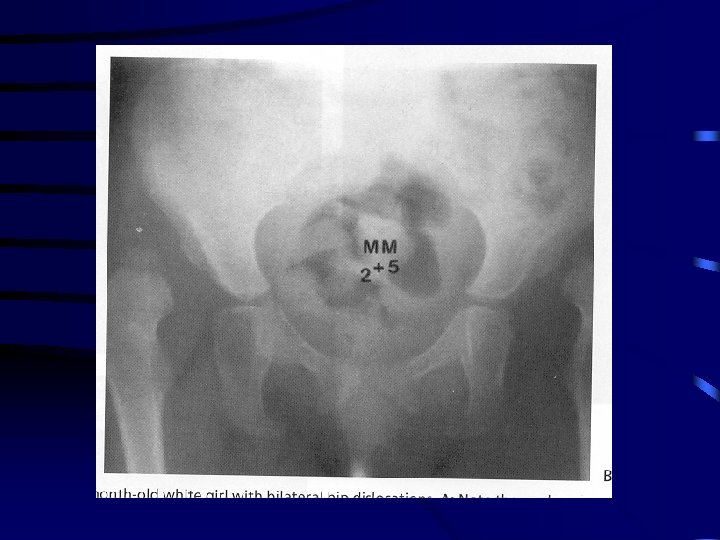

Radiological Diagnosis • classic features – increased acetabular index ( n=27, >30 -35 dysplasia) – disruption shenton line ( after age 3 -4 should be intact on all views) – absent tear drop sign – delayed appearance ossific nucleus and decreased femoral head coverage – failure medial metaphyseal beak of proximal femur , secondary ossification center to be located in lower inner quadrant – center-edge angle useful after age 5 ( < 20) when can see ossific nucleus

Radiography con’t • newborn period DDH not a radiographic diagnosis and should be made by clinical exam • after newborn period diagnosis should be confirmed by xray • several measurements • treatment decisions should be based on changes in measurements